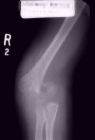

Fractura

Uma fractura é uma solução de continuidade no tecido ósseo. Em caso de fractura ou suspeita de fractura, o osso deve ser imobilizado. Qualquer movimento provoca dores intensas e deve ser evitado.